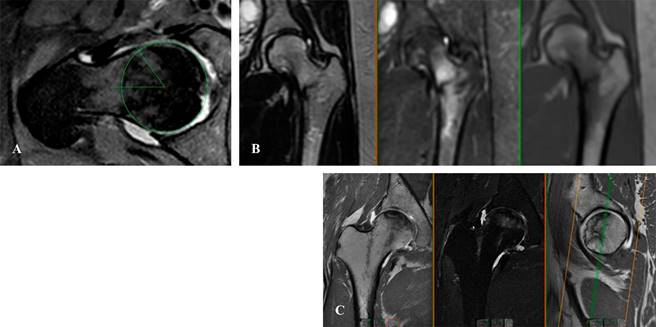

Resonancia magnética (RM)

De acuerdo con los criterios de imagen del Colegio Americano de Radiología Musculoesquelética, la resonancia magnética es el estudio estándar de oro para la evaluación de la cadera dolorosa en pacientes sin hallazgos anormales o patológicos en imagen radiológica. Para el abordaje de dolor no especificado o extraarticular, la resonancia simple es el estudio indicado; sin embargo, si la sintomatología es sugestiva de patología intraarticular, la artroresonancia de cortes finos (FOV [field of view]) es el estudio con mayor sensibilidad para dicho abordaje de valoración.16

El uso de artroresonancia ha revolucionado el diagnóstico de patología labrales y de cápsula, pudiendo comparar este estudio con los hallazgos artroscópicos. Se reporta una sensibilidad de 71%, especificidad de 44% y valor predictivo de 93% (Figura 12).17

Figura 12: A) Corte coronal en T1 de artroresonancia de cadera, se observa labrum anterosuperior. B) Misma lesión en secuencia T2 con supresión de grasa. C) Corte sagital en T1. D) Corte axial en secuencia T2, donde se realiza medición de ángulo alfa, con presencia de deformidad tipo cam de 3.7 mm.

No obstante, la resonancia de alta definición está llegando a sustituir este estudio de imagen más invasivo.16

Además del abordaje de patología intraarticular (Figura 13A), la resonancia magnética es de utilidad al identificar fracturas por estrés o fracturas patológicas (Figura 13B) cuya imagen no es claramente definida en estudio radiográfico simple. Se considera en estudio con mayor sensibilidad para la evaluación y diagnóstica de osteonecrosis (Figura 13C) y fractura por estrés.16,18